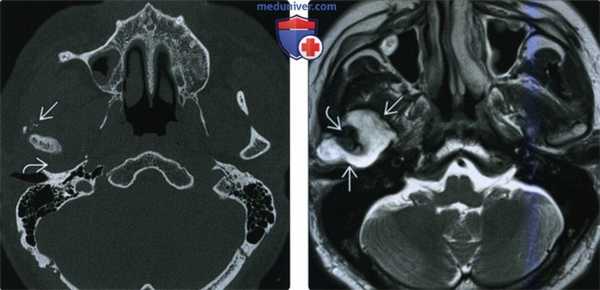

(Слева) При МРТ Т1ВИ в аксиальной проекции определяется объемное образование с сигналом промежуточной интенсивности, которое деформирует жевательное пространство и смещает кпереди заднюю стенку левой верхнечелюстной пазухи. Во всех последовательностях видны небольшие участки низкой интенсивности сигнала, которые представляют собой кальцификаты.

(Справа) МРТ Т2ВИ в аксиальной проекции, этот же пациент. Новообразование имеет гиперинтенсивный сигнал, характерный для опухолей хрящевой ткани. (Слева) МРТ Т1ВИ с КУ, аксиальная проекция, этот же пациент. Образование имеет неоднородную структуру и интенсивно накапливает гадолиний.

(Справа) КТ с КУ в аксиальной проекции, костное окно, этот же пациент. Определяется крупное новообразование, в толще которого «рассеяны» кальцификаты, образующие кольца и арки. Это типичные хрящевые кальцификаты. Наличие кальцификатов обычно говорит о низкой степени злокачественности опухоли.

(Слева) КТ в костном окне, аксиальная проекция. Типичная хондросаркома височно-нижнечелюстного сустава низкой степени злокачественности. Определяются небольшие кальцификаты дистрофической природы (либо кальцифицированный матрикс самого образования) и обширная деарукция/ремоделирова -ние суставной ямки.

(Справа) MPT Т2ВИ в аксиальной проекции, тот же пациент. Определяется дольчатое гиперинтенсивное образование с четкими контурами, которое окружает мыщелок нижней челюсти.